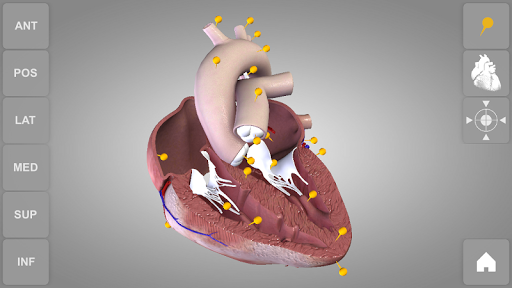

User can choose external view or section view. Moreover, the names of specific anatomical areas can be shown touching the related pins (available in the full version only).